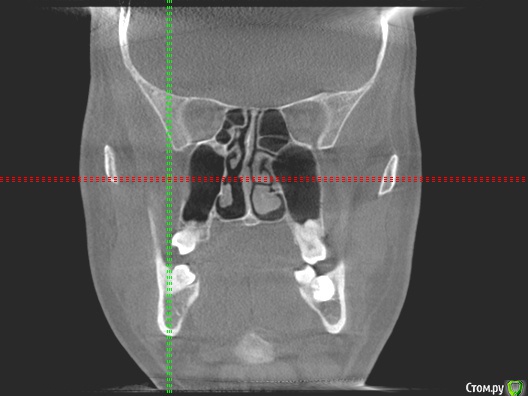

kozloff Опубликовано 15 ноября, 2015 Поделиться Опубликовано 15 ноября, 2015 Да, нужно исключить синусит.А еще можно заподозрить дисфункцию ВНЧС, на вашем снимке (ОПТГ) вызвает опасение расположение суставных головок. Но это может быть дефект снимка.Обязательно сделайте КТ, на одном снимке можно и пазухи рассмотреть, и ВНЧС. Ссылка на комментарий

kozloff Опубликовано 18 ноября, 2015 Поделиться Опубликовано 18 ноября, 2015 Подозреваю пульпит зуба 25И к лору не помешает сходить, есть отек слизистой. Гайморита нет. Ссылка на комментарий

Jurai Опубликовано 22 ноября, 2015 Поделиться Опубликовано 22 ноября, 2015 Есть проблема во фронтальном участке верхней челюсти: общая убыль костной ткани, ячеистая структура кости. смещение зубов так, что корни изогнулись, это значит, что либо резорбция (рассасывание) либо очень длительное уже идет воздействие. Могу подозревать новооборазование в этом участке.Вам нужна консультация челюстно-лицевого хирурга-онколога. 1 Ссылка на комментарий